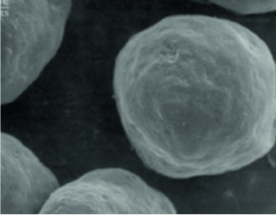

CaHA là một hạt hình cầu mịn, có kích thước đồng đều,

Hình dạng hạt với kích thước nhất định và bề mặt nhẵn cho phép nguyên bào sợi hoạt động tốt và được tối ưu hóa để sản xuất vật liệu tái tạo cho ECM (chất ngoại bào)

(nếu hạt phân tử sắc nhọn và không đều có thể xảy ra phản ứng viêm)

Radiesse

(25~45um/Microsphere)

Sản phẩm A

(30~60um/Crystal)

Sản phẩm B

(20~80um/không đều)

Nó duy trì hình dạng hình cầu trong suốt quá trình, cho thấy tác dụng thúc đẩy tái tạo collagen ổn định mà không gây kích ứng da.